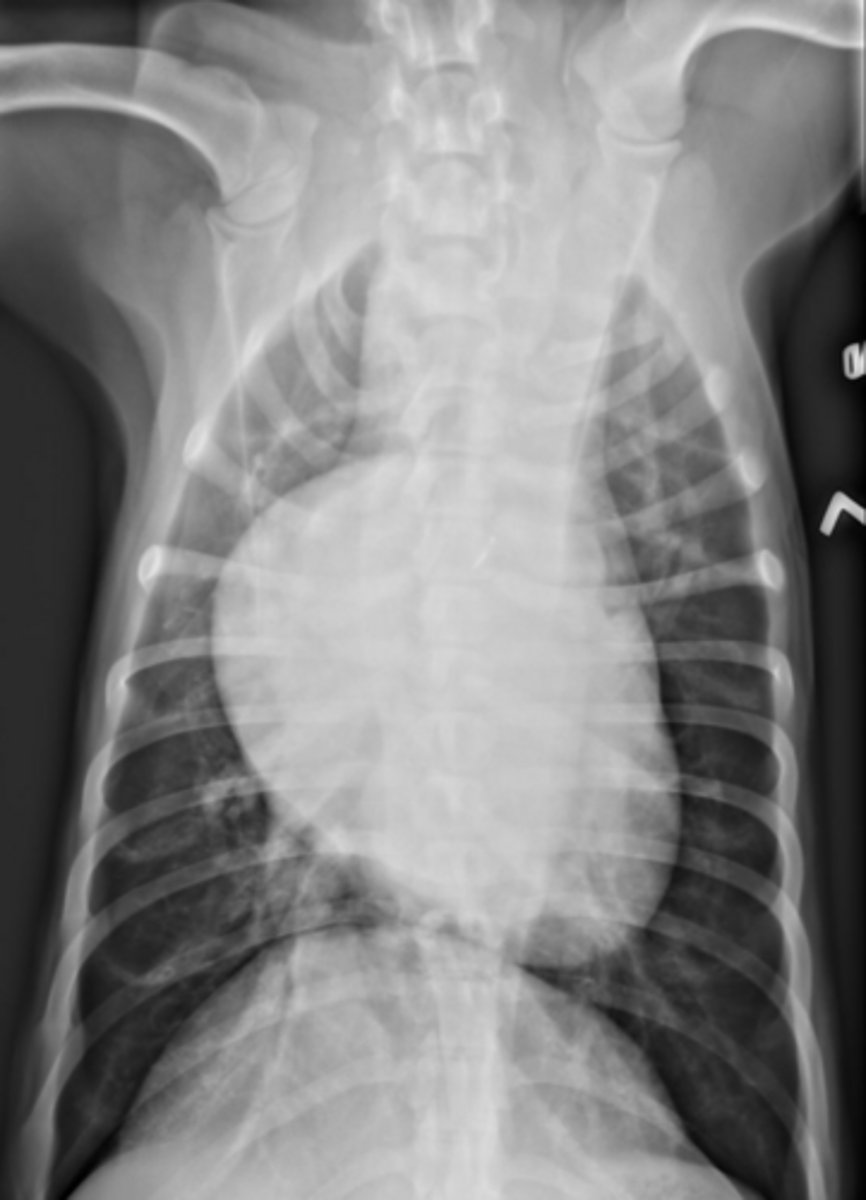

Yes

-VHS - 9.3

-Pulmonary pattern

A feline presents with the following rads. Are the in CHF?

CHF/HCM

A feline presents with the following rads. What is the dx?